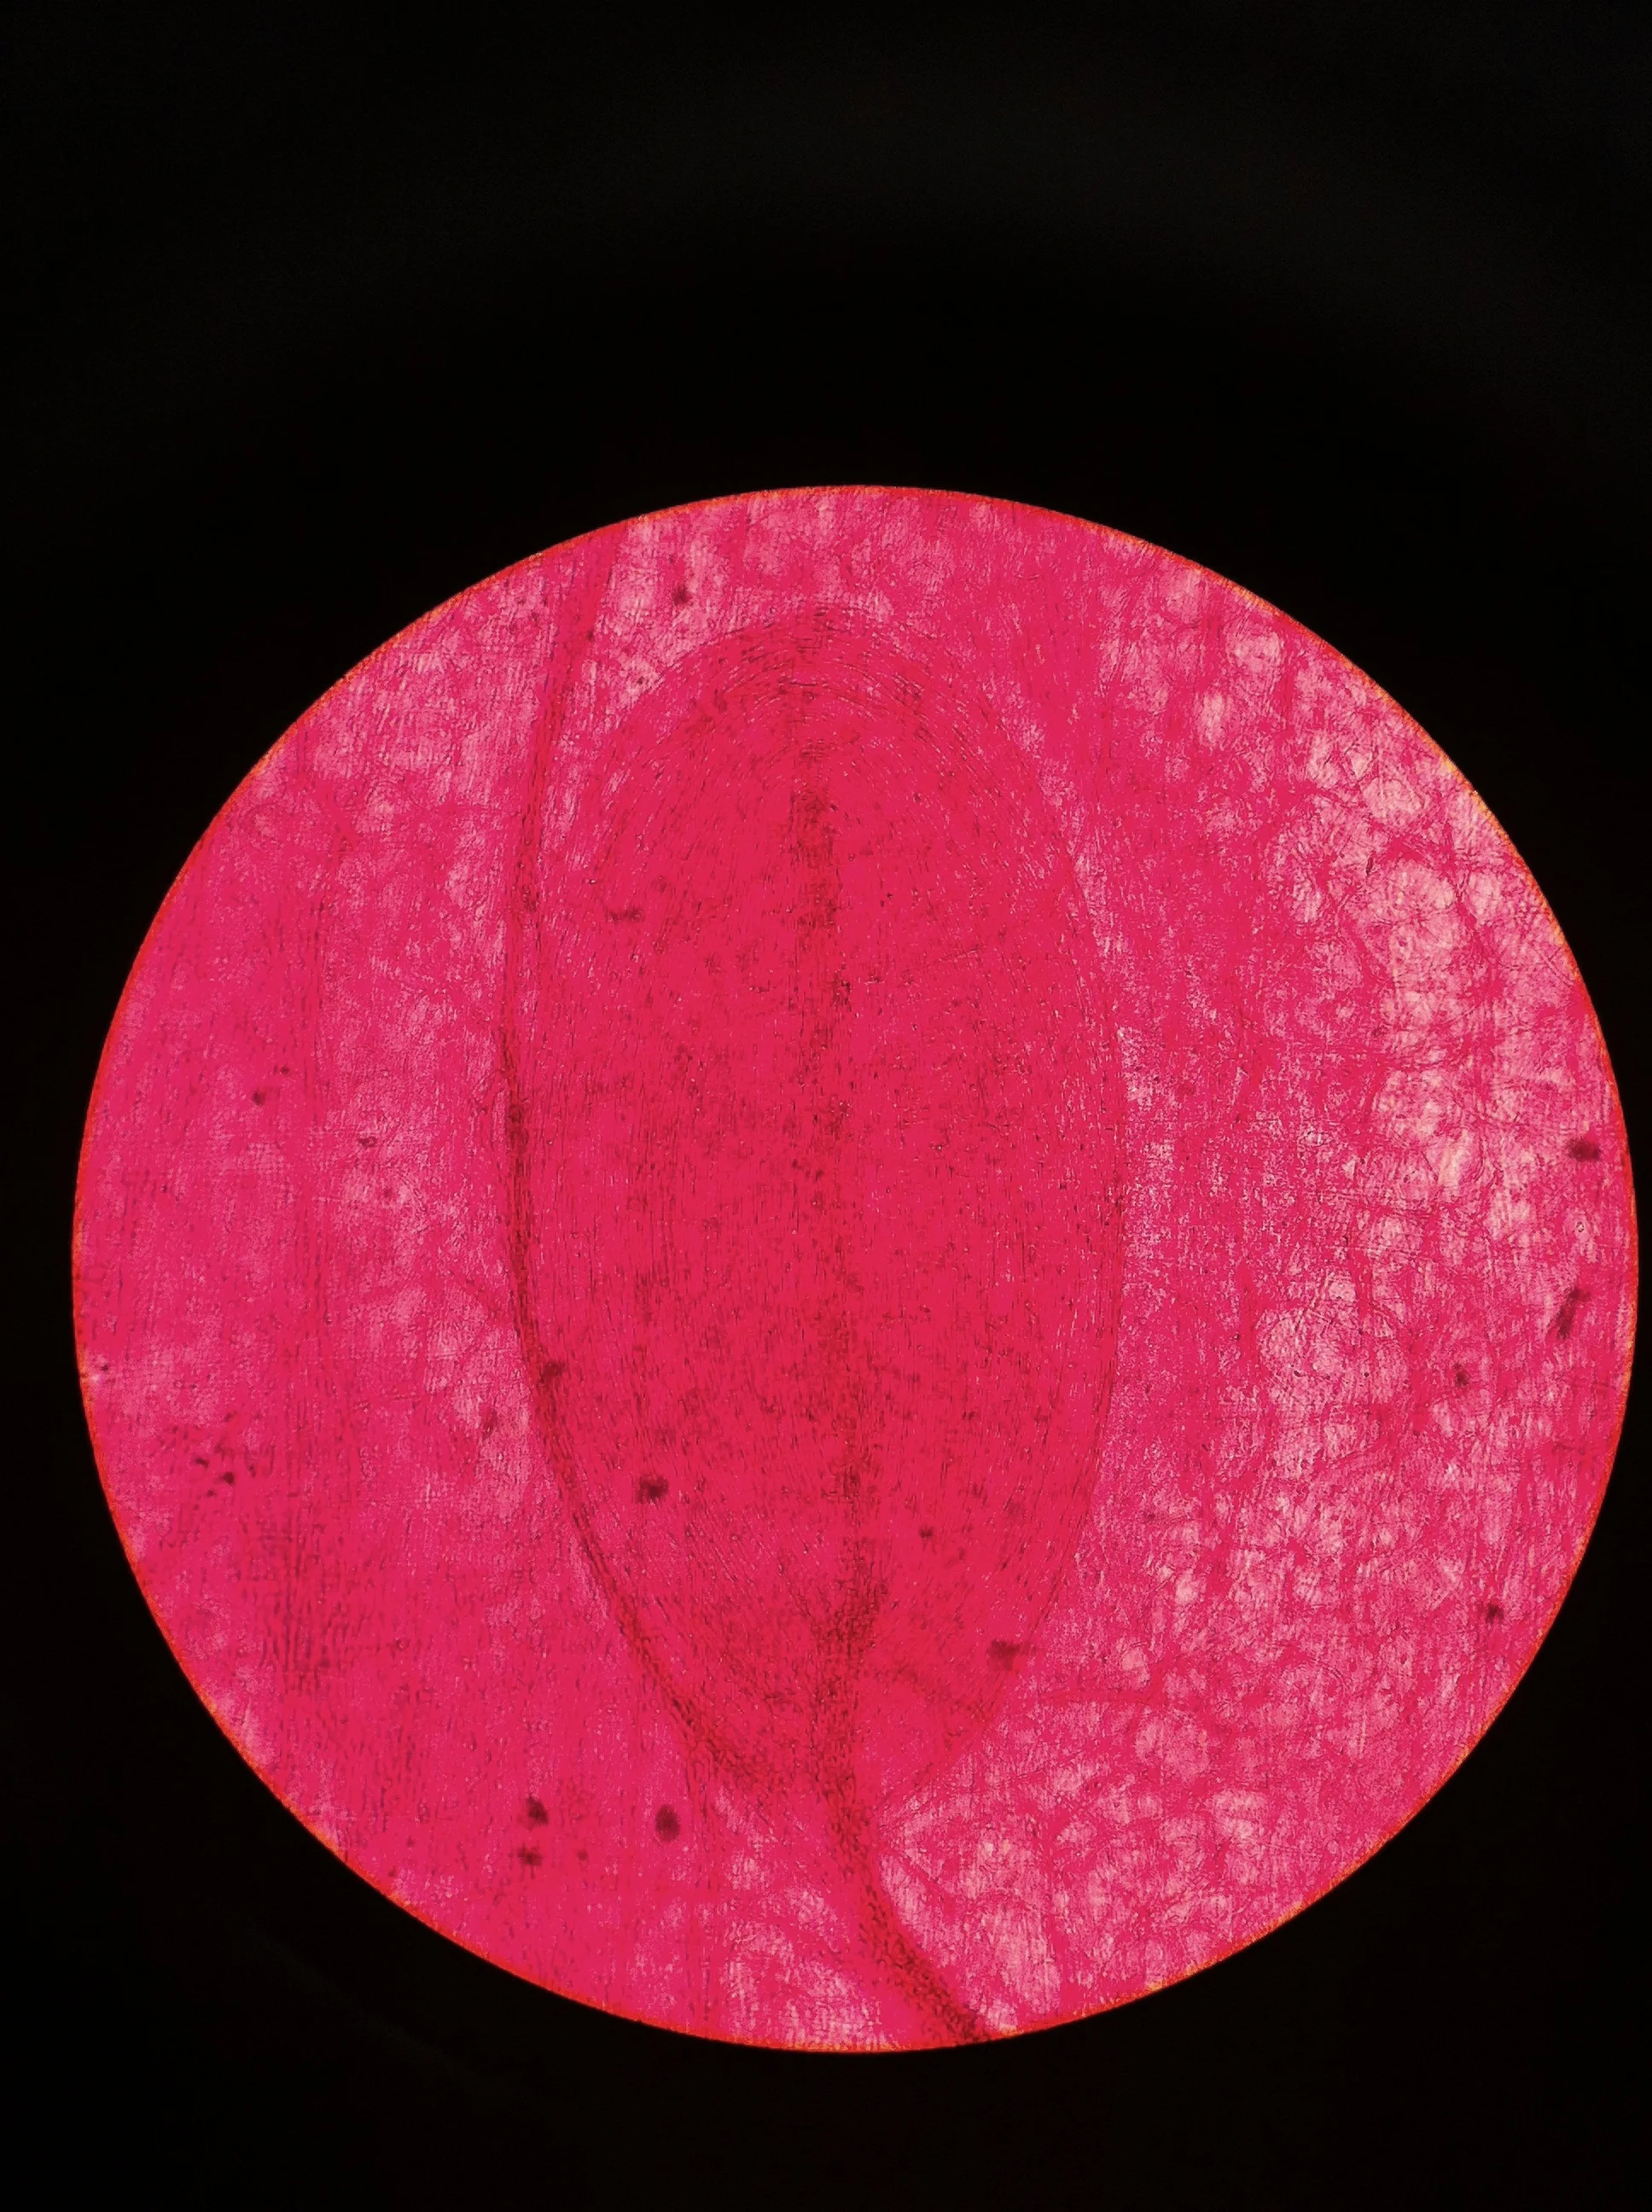

Pacinian Corpuscle 400X